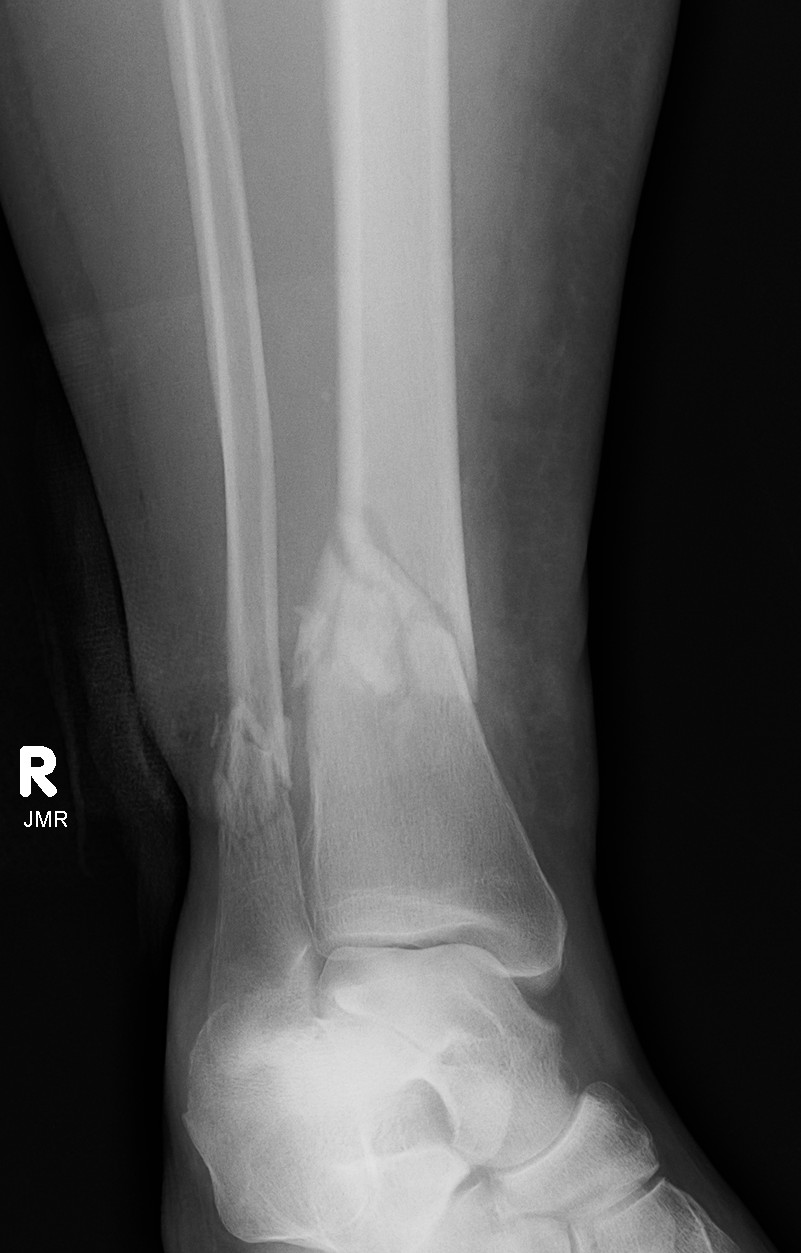

Distal Tibial Fractures

Definition

Metaphyseal

Extra-articular

Intra-articular Extension